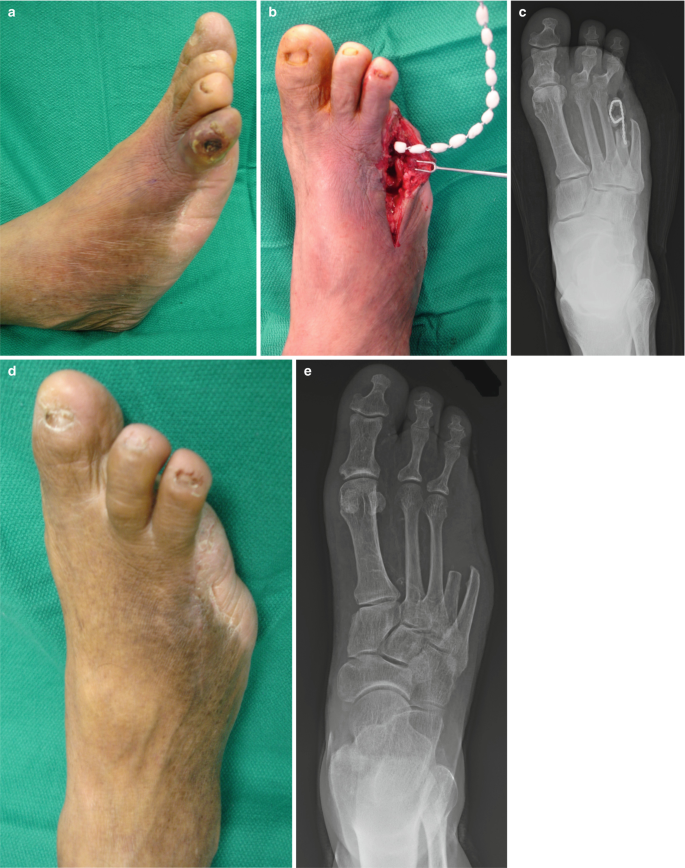

The Clinical Pictures Of King Classification Stage 1 Normal Foot Download Scientific Diagram

The Diabetic Foot Springerlink

Medicina Free Full Text Treating Diabetic Foot Osteomyelitis A Practical State Of The Art Update Html